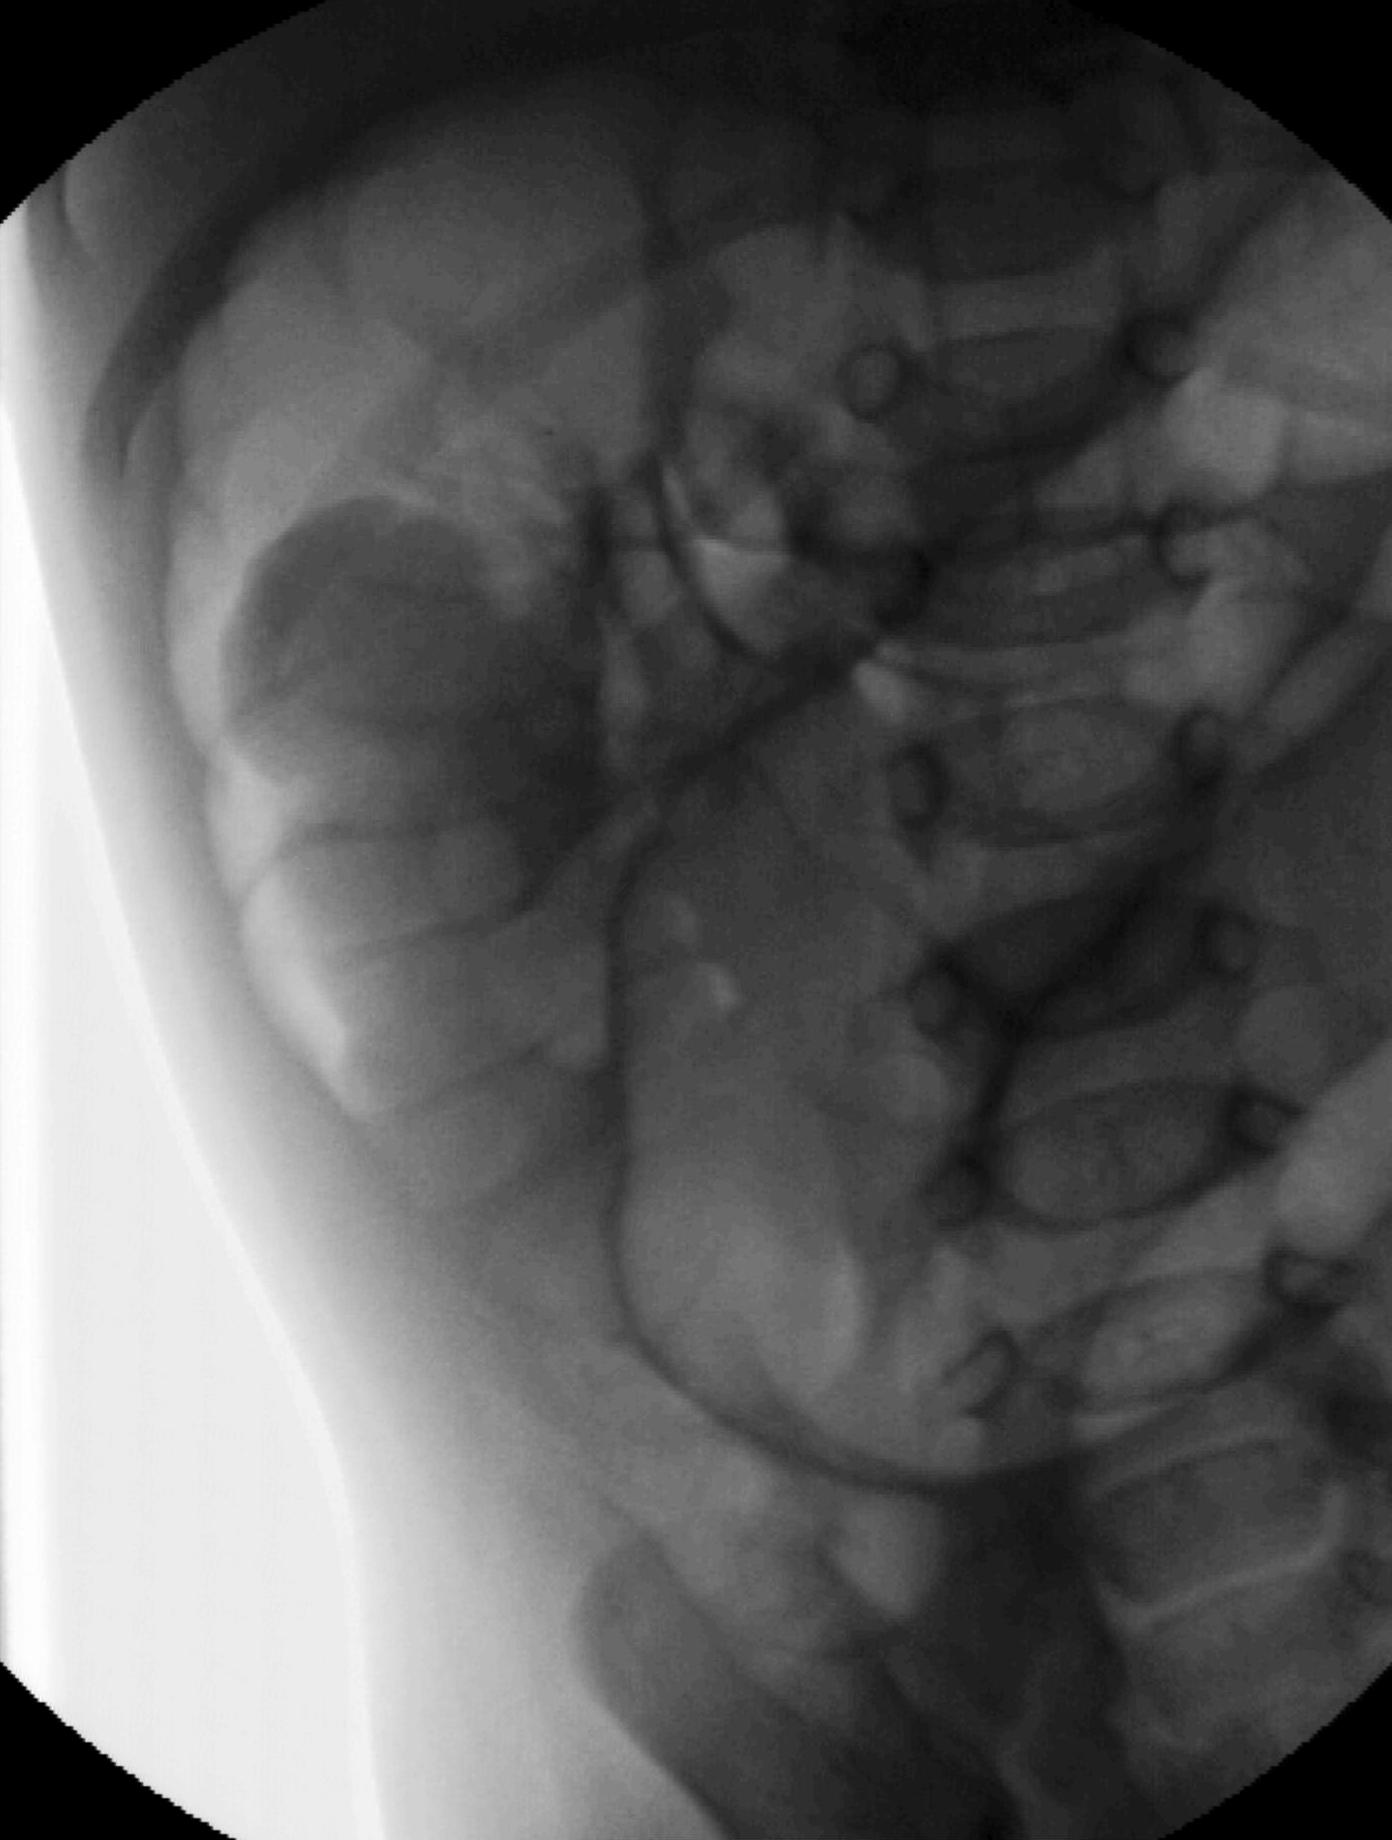

Image

22.The calices and the pyelon of the kidney are markedly dilated, the parenchyma is thinner. Severe hydronephrosis. The ureter is not visible. Pyelouretral stenosis.